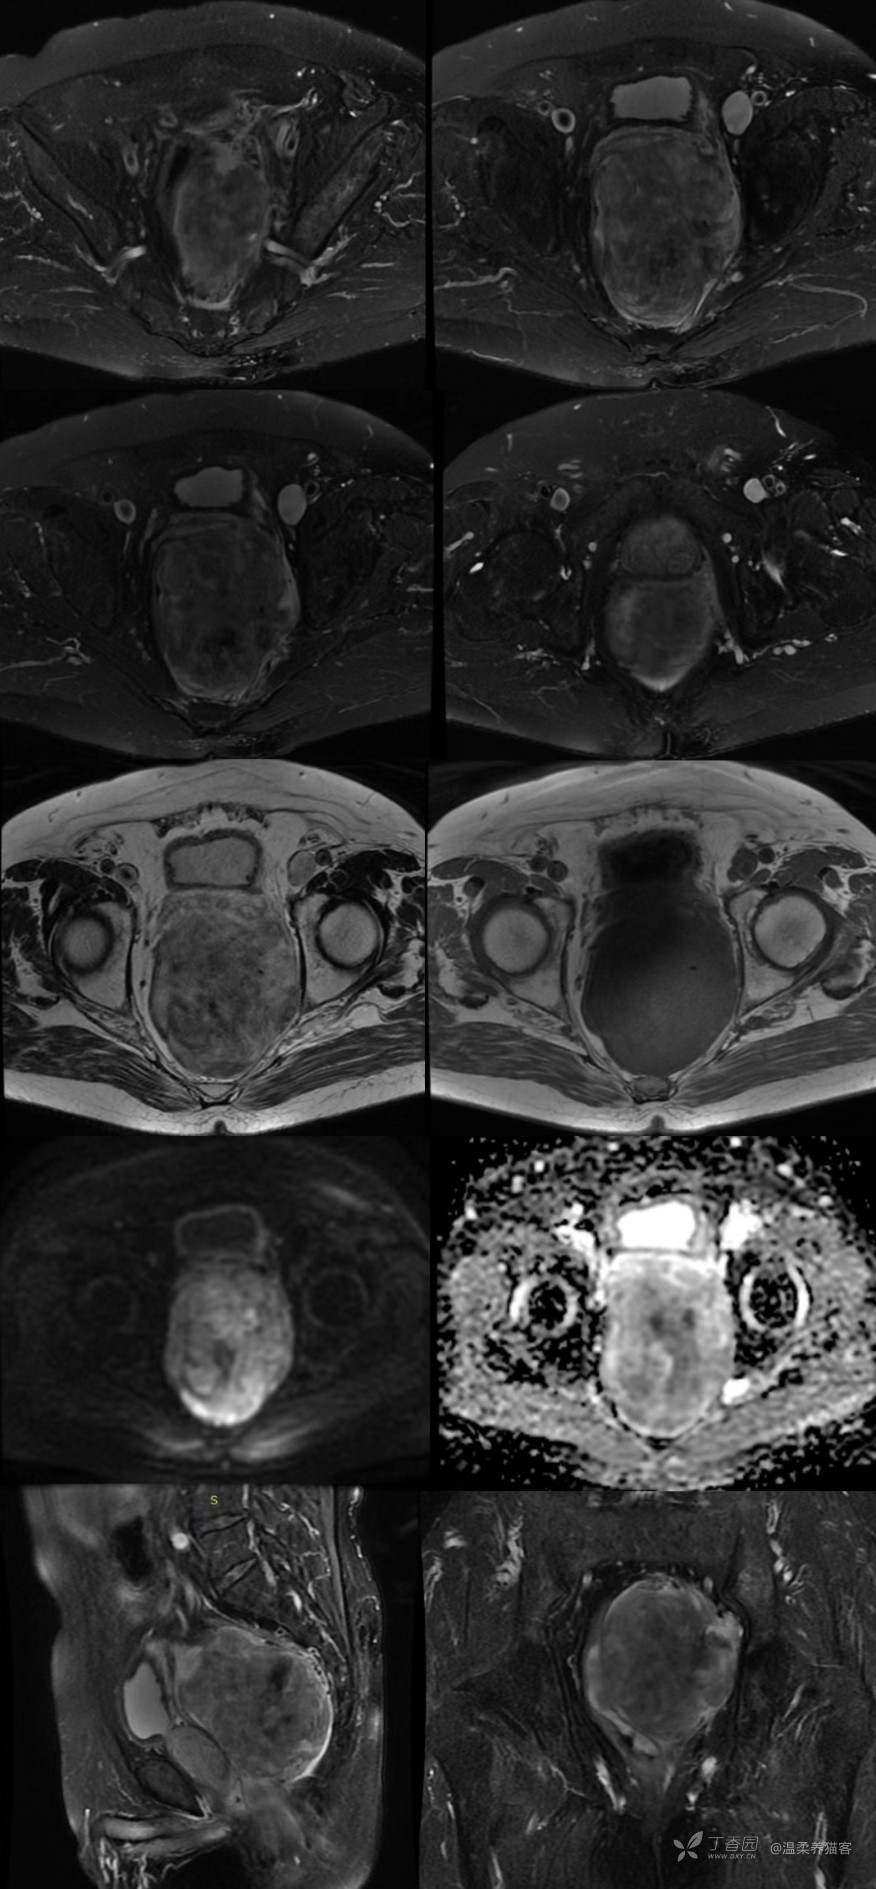

影像资料:MRI 平扫+CT 增强

MR 印象:直肠中下段左侧腹膜后可见一分叶状巨大肿块影,边界清晰,大小约 8.7 cm×8.0 cm×11.4 cm,T2WI 呈混杂高低信号,T1WI 呈等/稍低信号,DWI 呈局部高信号,对应 ADC 图信号减低;双侧盆壁、盆腔及腹膜后未见明确肿大淋巴结。

MR 诊断意见:盆腔左侧腹膜后肿块,考虑间叶组织来源的肿瘤可能性大,建议增强。

CT 印象:直肠中下段左侧腹膜后可见一巨大肿块影,边界清晰,大小约 9.0 cm×8.1 cm×11.3 cm,增强扫描呈不均匀强化,增强三期 CT 值分别约:35-85 HU,41-101 HU,37-94 HU,其中动脉期可见左侧髂内动脉及髂外动脉从肿块左缘穿入。肿块与直肠左侧壁分界欠清,邻近直肠受压右移。肿块周围可见多发条絮样及条片样渗出性改变。盆腔、腹膜后及双侧盆壁未见明确肿大淋巴结。

诊断意见:盆腔腹膜后肿物,考虑间叶组织或神经源性肿瘤,请结合 MR 影像。